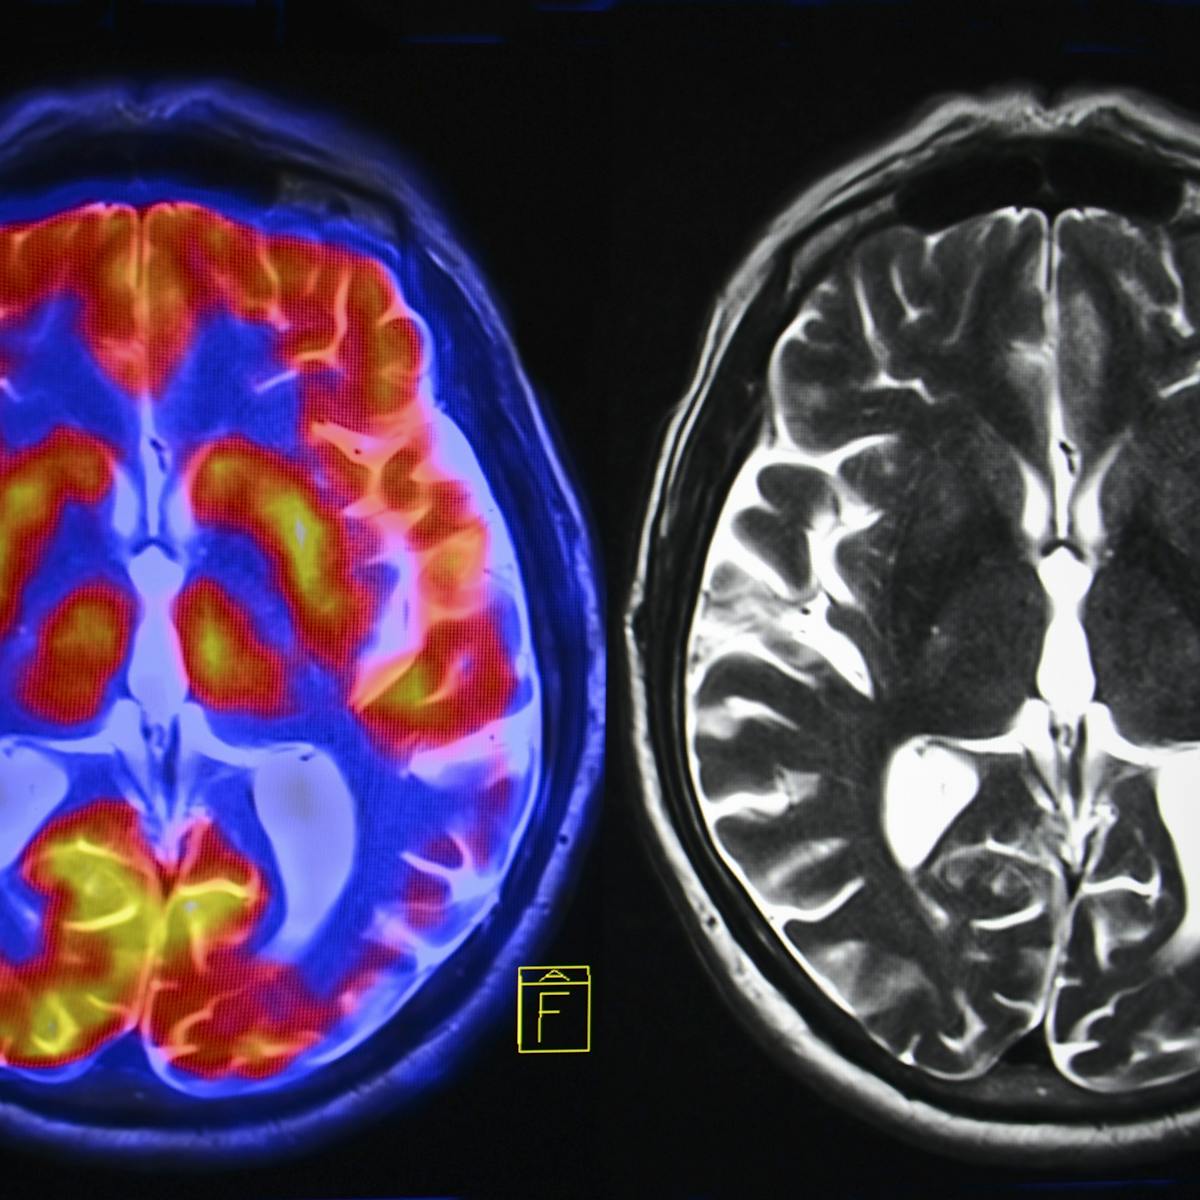

Its believed that many who suffer from depression either do not receive treatment or dont let their. Depression is generally a type of mood disorder that causes emotional problems. Brain imaging studies using MRI scanning show that these common day-to-day depression symptoms are associated with abnormalities in specific areas.

Major depressive disorder MDD is diagnosed when patients show 5 of the symptoms below on a daily basis for longer than two weeks. In people with depression the limbic system has had a disruption or overactivation. Here is a diagram of the affects of depression circled in red are different parts of the brain.

In turn these differences may affect the brains ability to process emotional stimuli and respond to new environmental stresses. Comparison of a depressed brain and a not depressed brain. Experts arent sure what causes these changes.